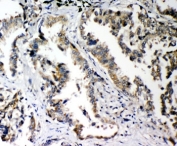

IHC-P: PLK2 antibody testing of rat intestine tissue. HIER: steam section in pH6 citrate buffer for 20 min and allow to cool prior to staining.